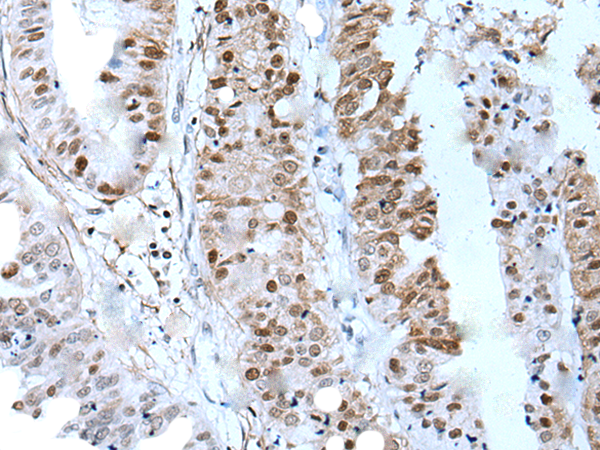

中文名稱:兔抗ZNHIT3多克隆抗體

英文名稱: Anti-ZNHIT3 rabbit polyclonal antibody

ZNHIT3 (zinc finger, HIT-type containing 3), also known as TRIP3 (thyroid receptor-interacting protein 3) or HNF-4a coactivator, is a 155 amino acid protein that contains one HIT-type zinc finger and regulates PPAR -mediated adipocyte differentiation. ZNHIT3 also coactivates HNF-4 , and as a thyroid receptor interacting protein, ZNHIT3 interacts with the ligand binding domain of the thyroid receptor. The gene encoding ZNHIT3 maps to human chromosome 17, which comprises over 2.5% of the human genome and encodes over 1,200 genes. Two key tumor suppressor genes are associated with chromosome 17, namely, p53 and BRCA1. Malfunction or loss of p53 expression is associated with malignant cell growth and Li-Fraumeni syndrome. Like p53, BRCA1 is directly involved in DNA repair, though specifically it is recognized as a genetic determinant of early onset breast cancer and predisposition to cancers of the ovary, colon, prostate gland and fallopian tubes.

Applications:

ELISA, IHC

IHC positive control:

Human esophagus cancer and human tonsil

IHC Recommend dilution:

45-300